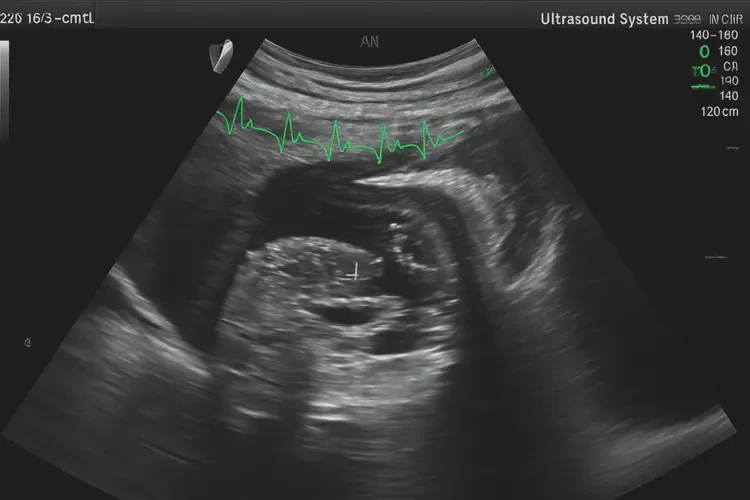

早期胎心率:在怀孕6-8周时,胎心率的正常范围是100-180次/分钟。此时,胎心率可能会有一定的波动,但只要在这个范围内,就不必过于担心。

中期胎心率:在怀孕12-20周时,胎心率的正常范围是120-160次/分钟。此时,胎心率相对稳定,但仍需定期监测。

晚期胎心率:在怀孕20周以后,胎心率的正常范围仍然是120-160次/分钟。此时,胎心率的波动可能会减少,但仍需注意异常情况。